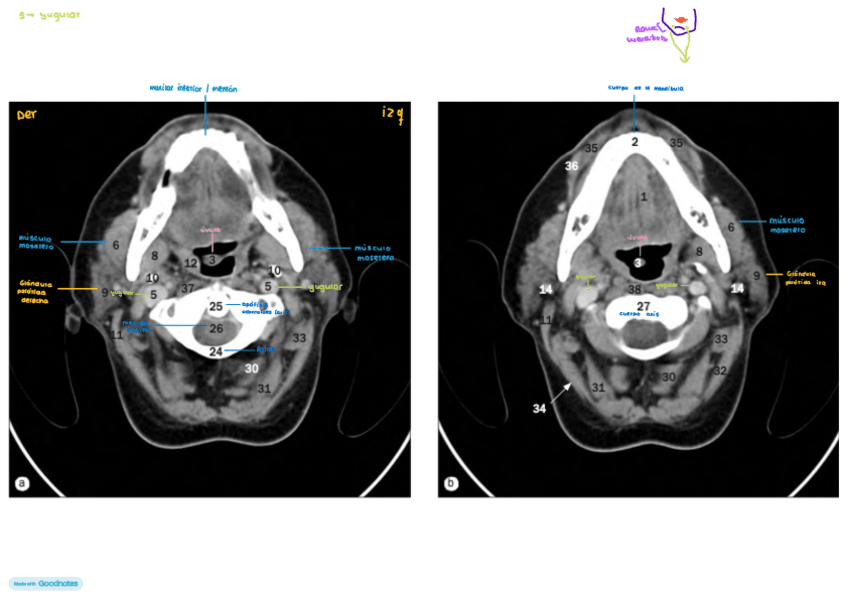

IMAGENES-AXIALES-DE-CUELLO-con-anatomia.pdf